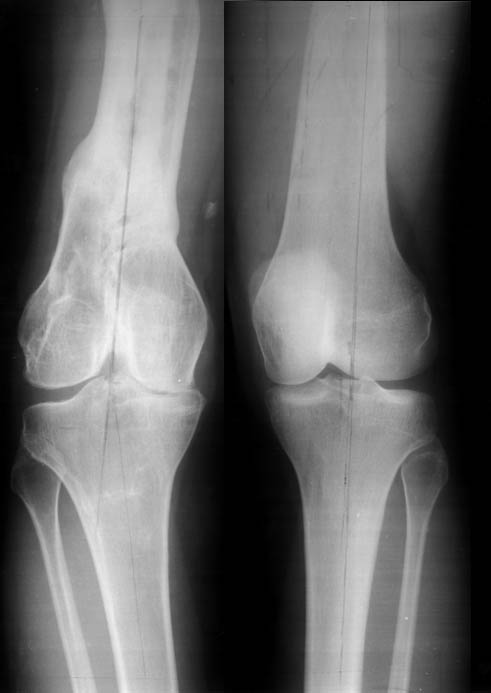

Прежде всего необходимо выполнить рентгенографию в таком положении, как это показано на рис.

После этого представится возможность оценить ось и сравнитьеё с нормой Рисунки из кники Dror Paley - Принципы коррекции деформаций. Этой теме посвящены 800 страниц. Хотя, учитывая контрактуру, это исследование не будет исчерпывающим.

Согласно тому же Палею следует выделять 4 причины деформации (вальгусной или варусной) в области коленного сустава. Это требует выполнения доплнительных снимков (с распоркой в области колена и пр...).

Но этому, как я писал, посвящены 800 страниц и около тысячи рисунков.